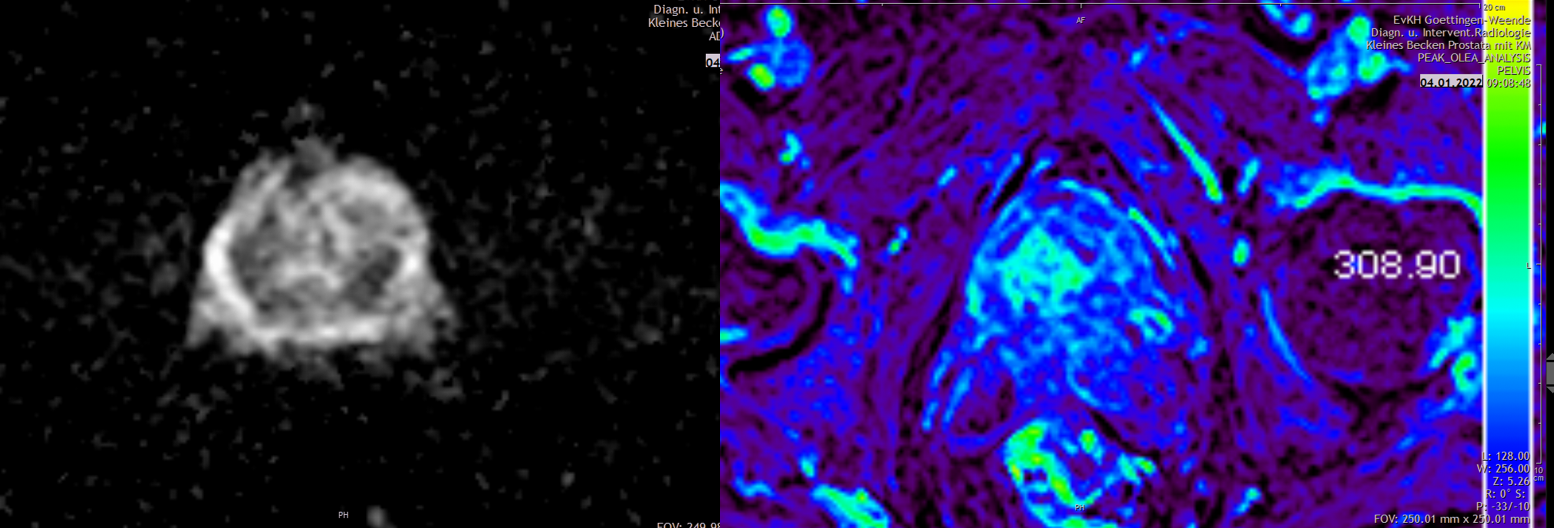

Urogenitale Radiologie, multiparametrische Prostatabildgebung

Es handelt sich um ein medizinisches MRT-Bild des Beckens, das die Prostata darstellt.

Es zeigt medizinische Bildgebung des Beckens mit farblich hervorgehobenem Bereich, möglicherweise zur Analyse von Gewebe.

Aufgaben der urogenitalen Radiologie sind – neben nichtonkologischen Krankheitsbildern wie Nierensteinen – die Darstellung und Charakterisierung von urologischen Neoplasien, die Suche nach ihren Metastasen im Rahmen des Tumorstagings, die Therapiekontrolle und die radiologische Tumornachsorge. Häufig untersuchte Tumore sind das Nierenzell-, Blasen- und Prostatakarzinom. In unserem Institut setzen wir mit der 80-Zeilen Multidetektor-CT und der 3 Tesla MRT hochmoderne Untersuchungsverfahren ein. Diese werden kontinuierlich weiterentwickelt und dem Stand der Wissenschaft angepasst. So hat sich in den letzten Jahren beispielsweise das multiparametrische MRT (mpMRT) der Prostata als optimales Verfahren bewährt, um Prostatakarzinome zu entdecken und darzustellen. Mit dieser strahlungsfreien Methode können wir Tumorherde identifizieren und klassifizieren. In der Abteilung für Urologie können so gezielt Gewebeproben entnommen werden, die auch kleinste Tumorareale erfassen. Wir nutzen bei urologischen Tumoren in besonderen klinischen Situationen nicht nur die bildgebende Diagnostik, sondern auch therapeutische interventionell-radiologische Verfahren, wie die Embolotherapie bei Neoplasien der Nieren.

MRI-Bild der Prostata, Umrisse und Parameter eines Tumors, Diagramme zur Fortschrittanalyse, Olea Medical-Logo.